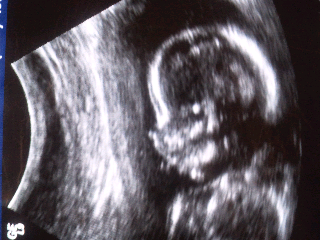

Today was our ultrasound! Baby W2 is either on track and growing as s/he should be. We will get an official report next week at our doctors appointment. I'll post more on the ultrasound later but for now I'll leave you with this picture of our little cutie. Oh, and no we didn't find out the sex...want to save the surprise for the big day as we did with Forrest :)